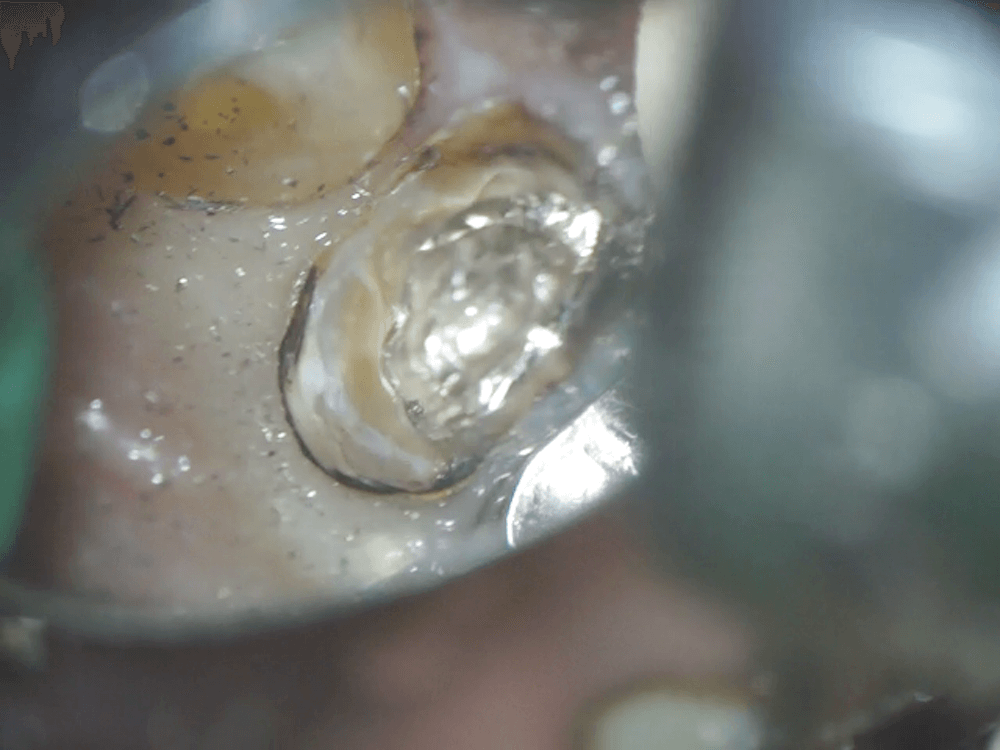

マイクロスコープで確認したポストです。銀色のものがそうです。

これを、新品の除去バーを使って、余計な歯を削らないよう、慎重に取り除いていきます。